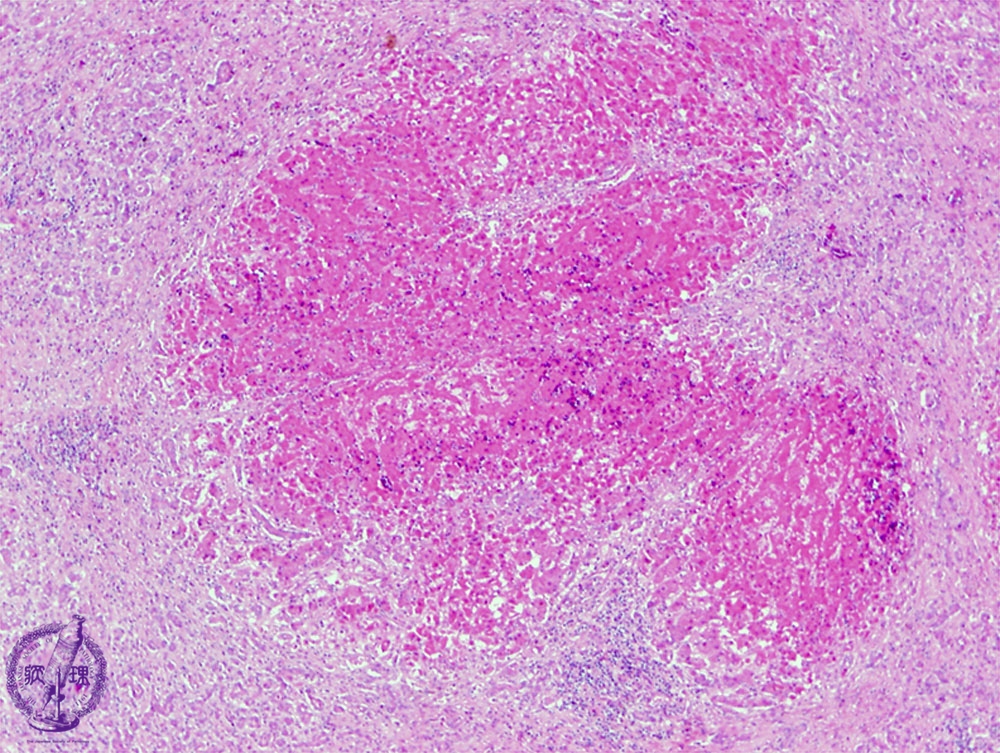

- ★(3)Fulminant hepatitis

Microscopic finding (HE stain, low power view): Irregular necrotic foci show eosinophilic change.